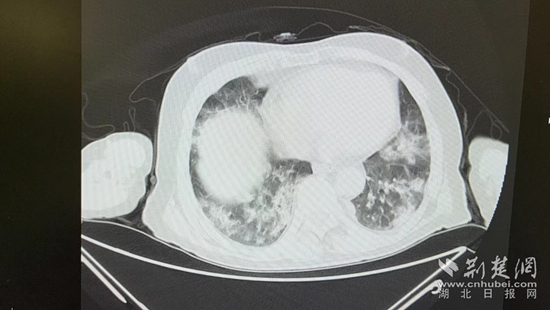

病情的突然惡化,會不會與近期的新冠病毒感染有關?雖然家屬反映,曾多次在家自測抗原正常,但徐濤還是力排眾議,說服老人進行核酸檢測和肺部CT檢查。結(jié)果顯示核酸陽性,60%白肺,結(jié)合老人的表現(xiàn),這正是一例典型的老年人“沉默性肺炎”。

胸部CT片。通訊員 供圖